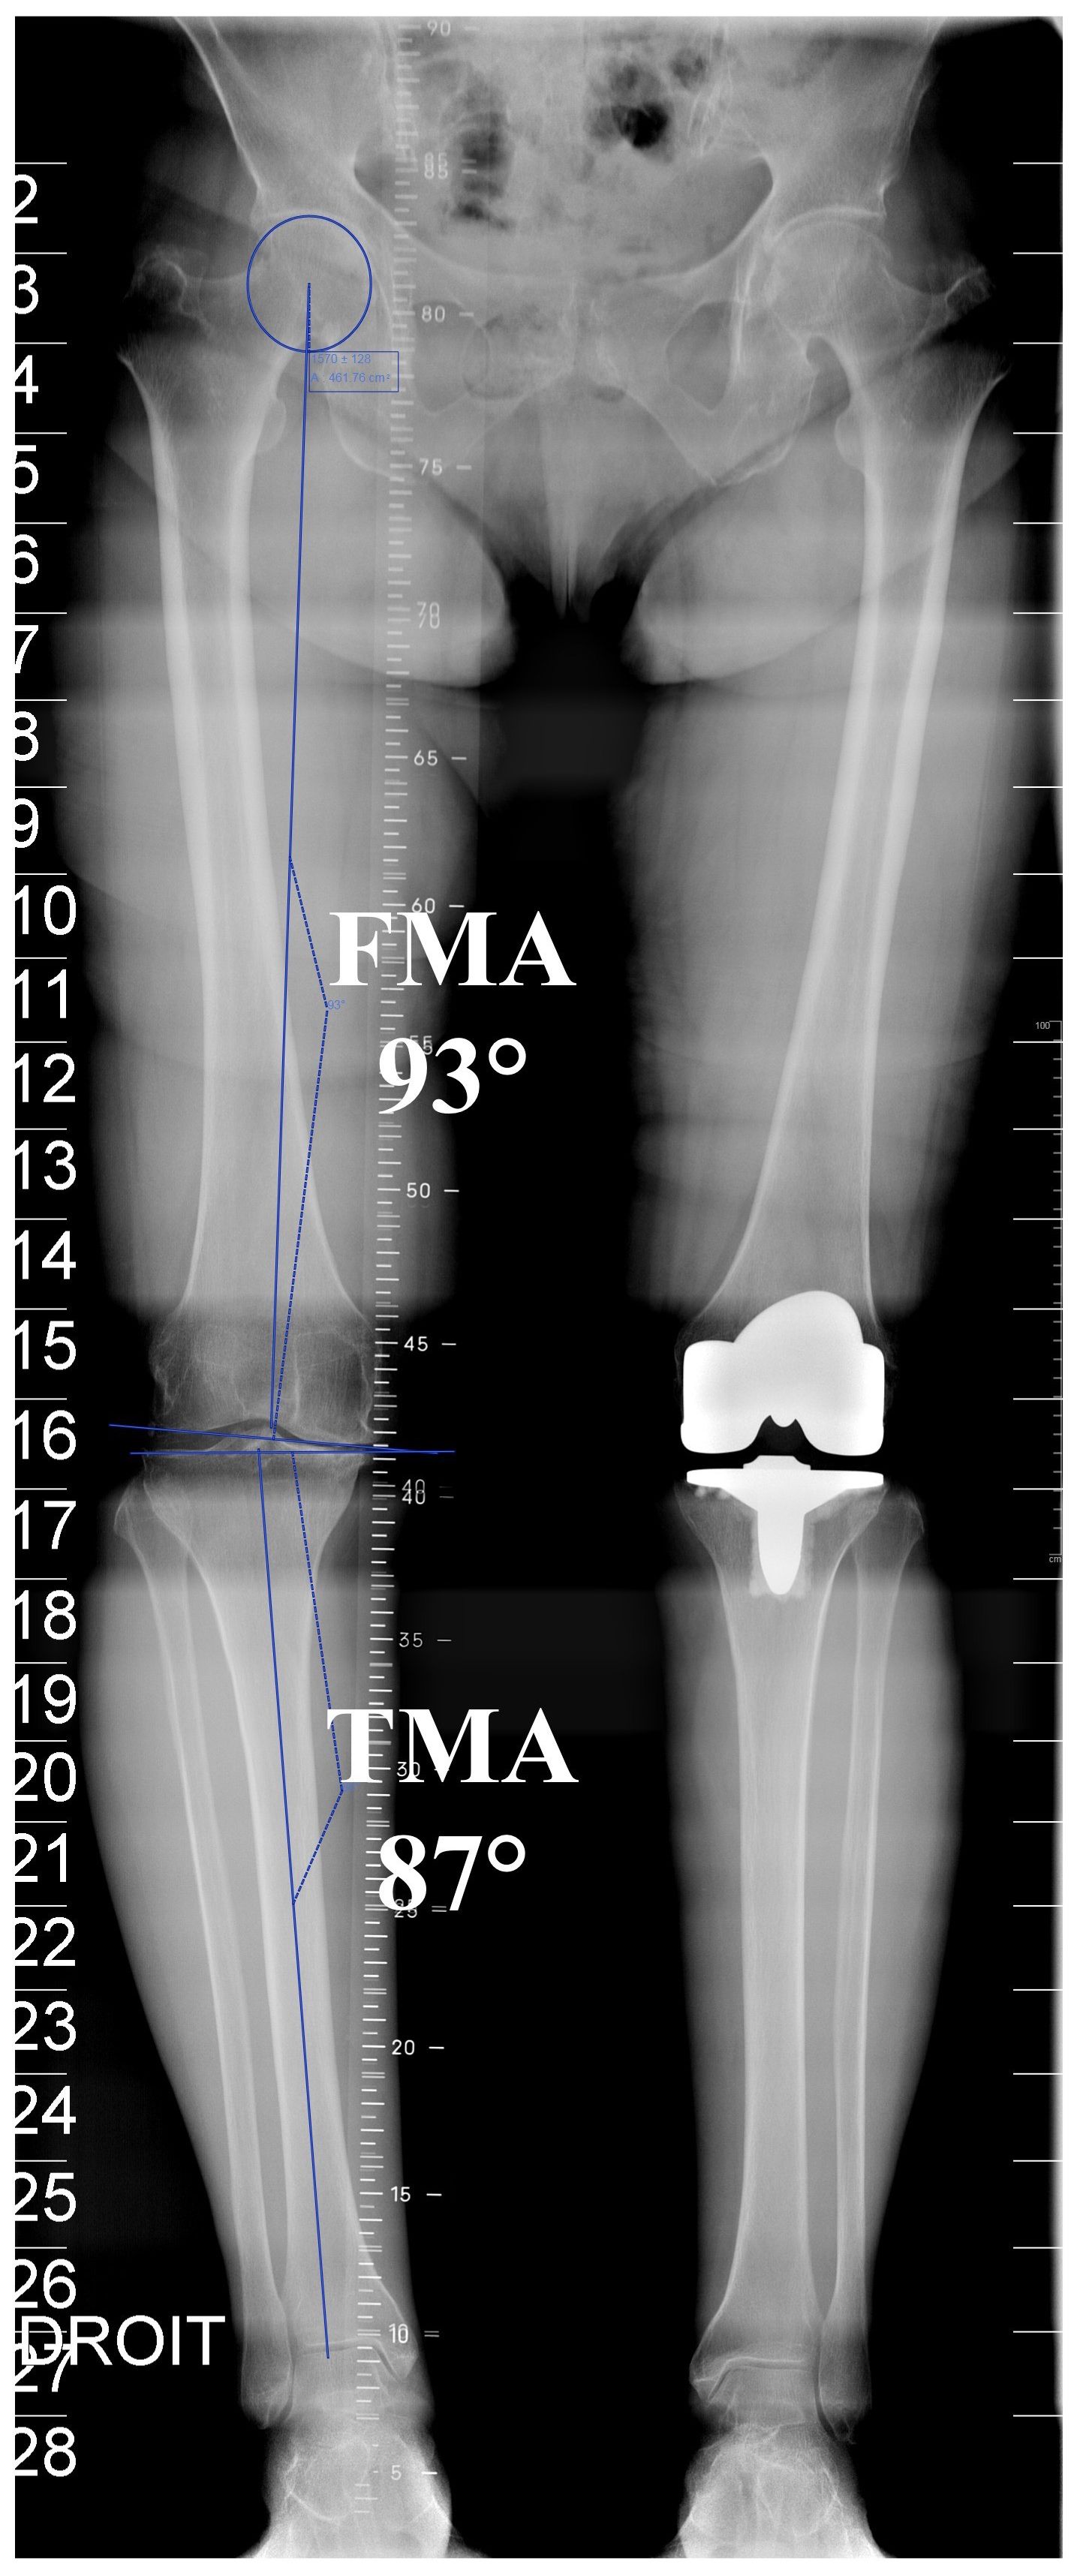

First, it is important to clarify that lower limb alignment is referenced against a vertical midline centred over the pubic symphysis. The anatomical axes are lines drawn along the length of the intramedullary canals of the femur and tibia. The mechanical limb axis is a line drawn from the centre of the head of femur to the centre of the talus and is referred to as Maquet’s or Mikulicz’s line. Provided there is no osteoarthritic degeneration of the knee, at the tibia the mechanical alignment usually matches the anatomical alignment, with a tibial mechanical-anatomical (TMA) angle of 0°, or neutral. In contrast the anatomical and mechanical axis of the femur are different and show a wide variation from 0 to 12° of valgus with an average femur mechanical-anatomical (FMA) angle of 6°. The distal femoral joint surface has an inclination of about 3° of valgus and the proximal tibia joint surface of about 3° of varus to the mechanical axis. This includes that the femorotibial joint line shows an inclination of 3° varus (Figure 2).

Considering these definitions, overall alignment can be described in two ways, using either the anatomical femoral-tibial (AFT) angle or the mechanical femoral-tibial (MFT) angle. The AFT angle is simply the angle between the anatomical axis of the distal femur and the anatomical axis of the proximal tibia. In a normal knee the AFT should be about 6° of valgus (range 4 to 9°). The MFT represents the angle between the mechanical axis of the femur (centre femoral head and centre distal femur) and mechanical axis of the tibia (centre proximal tibia and centre ankle). In a normal knee the MFT should be neutral 0° (range 3° valgus to 3° varus). While the AFT angle can be estimated from standard (short-leg) radiographs, measurement of the MFT angle requires long-leg radiographs (Figure 3). The AFT does not represent the real lower limb alignment and allows pure guessing of the mechanical axis of the lower limb.